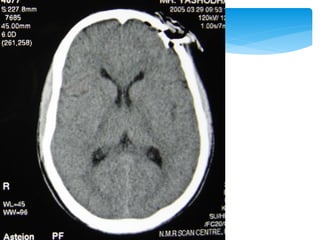

Approach To CT ScanCT scan

 Appearance of the normal structures

Approach To CTScanCT scan Bone window Look for fractures- •Cranial vault •Skull base •Facial bones Tissue window •EDH •SDH •ICH •Contusions •Pneumocephalus •Hydrocephalus •Cerebral edema Subdural window •Any hemorrhage •Soft tissue and bone •Fontanel •Suture lines •Foreign bodies

 Appearance ofthe normal structures CT Scan